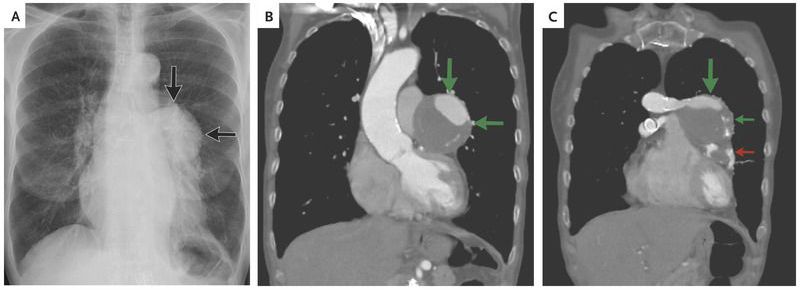

A 78-year-old woman who had undergone coronary-artery bypass graft surgery 30 years earlier and had a smoking history of 54 pack-years presented to the emergency department with shortness of breath and fatigue. The troponin level was within the normal range. There was no evidence of ischemic changes on electrocardiography. Radiography of the chest revealed a mediastinal, hilar mass lesion on the left side (Panel A, arrows). Computed tomographic angiography of the chest revealed two partially thrombosed aneurysms of the saphenous-vein grafts. The larger aneurysm arose from the superior graft that was anastomosed to the left anterior descending coronary artery (Panel B, arrows; Panel C, green arrows), and the smaller aneurysm arose from the inferior graft, which was anastomosed to the diagonal artery (Panel C, red arrow). In view of the risks of undergoing surgery again and the absence of angina, the patient continued to pursue a conservative course and the symptoms at presentation resolved. The patient was lost to follow-up.